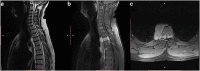

Methods: A 39-year-old man presented with signs of spinal cord compression for the past 2 weeks. His medical history was consistent for an asymptomatic right iliac wing mass that appeared 3 years ago and for which he has not consulted. Magnetic resonance imaging revealed multiple bony lesions of the thoraco-lumbar spine associated with a 6-cm right paravertebral mass at the T4 level extending posteriorly through the intervertebral foramina to the spinal canal causing major spinal cord compression. An emergent T2-T6 laminectomy allowed for a complete resection of the epidural mass. Pathological examination confirmed the diagnosis of well-differentiated liposarcoma. Adjunctive radiation therapy was administered.